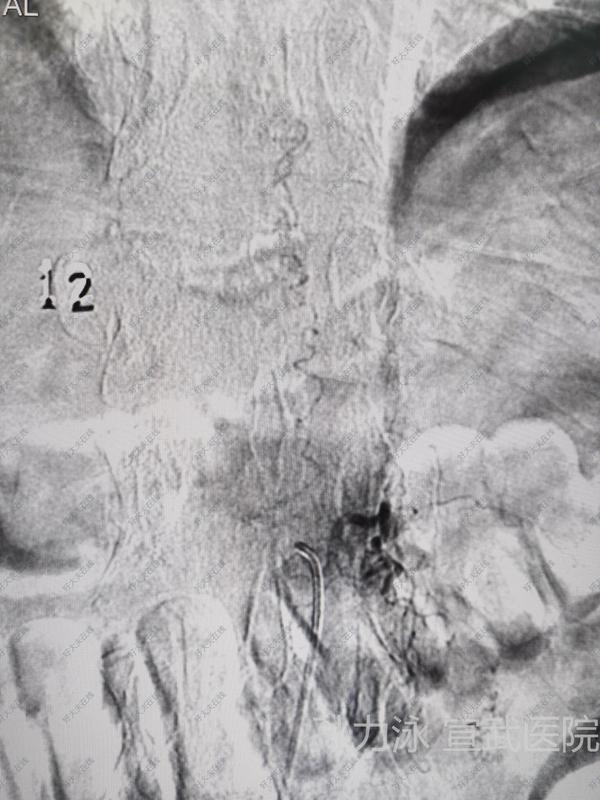

硬脊膜動靜脈瘺逐步排查瘺口,精準(zhǔn)治療硬脊膜動靜脈瘺診斷的金標(biāo)準(zhǔn)是選擇性血管造影(DSA),不僅可以定性診斷,還可以明確瘺口的位置。主要治療方式有手術(shù)夾閉瘺口和血管內(nèi)栓塞,手術(shù)方式治療的核心在于半椎板開椎夾閉或切斷瘺口

治療前病人女性,44歲,因左下肢乏力麻木2月加重伴胸背部疼痛不適1月余入院。病人2月前無明顯誘因出現(xiàn)左下肢乏力麻木,當(dāng)時未予重視,以為是疲勞所致。1月前上述癥狀加重,并出現(xiàn)了胸背部疼痛不適,在當(dāng)?shù)蒯t(yī)院就診,查胸髓磁共振,提示胸3-4水平脊髓異常信號,考慮海綿狀血管瘤可能,為求進(jìn)一步診治來我院。查體:神志清楚,雙上肢肌力肌張力正常,左下肢肌力IV級,右下肢肌力V級。復(fù)查胸段脊髓磁共振,提示胸3-4水平脊髓髓內(nèi)見一梭形異常信號影,大小約7mm,T1WI呈等信號,T2WI呈稍高信號影,周圍見低信號環(huán),增強(qiáng)掃描強(qiáng)化不明顯。診斷考慮胸3-4水平隱匿性血管畸形伴出血。治療后治療后0天術(shù)后即刻雙下肢活動良好。治療后2天術(shù)后48小時復(fù)查脊髓磁共振,提示畸形血管團(tuán)切除滿意。治療后7天術(shù)后1周病人可以正常下床行走,無神經(jīng)功能障礙。病理報告證實為血管畸形。